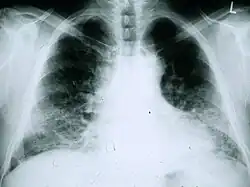

Chest X-rays are useful in the follow-up routine of IPF patients. Plain chest X-rays are unfortunately not diagnostic but may reveal decreased lung volumes, typically with prominent reticular interstitial markings near the lung bases.[3]